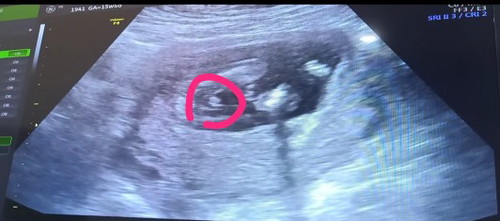

หมอบอกผู้ชาย 80% มีใครเคยอัลตร้าซาวด์เป็นชาย แต่ผิดพลาดเป็นหญิง อะไรอย่างนี้มีไหมค่ะ 15 week 5 day

บ้านนี้ตอน 13 w บอกว่าผุ้ชาย พอ 17 w บอกว่าผุ้หญิง😅😅😅หมอไม่แน่ใจคะ เพราะยังเห็นไม่ชัด ถ้าจะชัวรเลยต้องรอ 20-24 w ขึ้นไปค่ะ